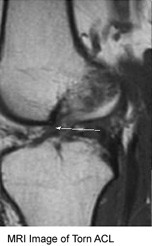

Orthopedic Surgery

Sports Medicine

MRI Image of Torn ACL